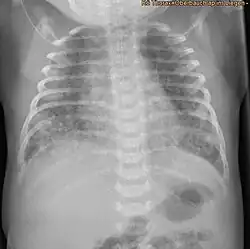

X-ray showing the extent of lung epithelial damage in response to meconium seen in neonates with meconium aspiration syndrome.

Respiratory distress in an infant born through the darkly coloured MSAF as well as meconium obstructing the airways is usually sufficient to diagnose MAS. Additionally, newborns with MAS can have other types of respiratory distress such as tachypnea and hypercapnia. Sometimes it is hard to diagnose MAS as it can be confused with other diseases that also cause respiratory distress, such as pneumonia. Additionally, X-rays and lung ultrasounds can be quick, easy and cheap imaging techniques to diagnose lung diseases like MAS.[16]